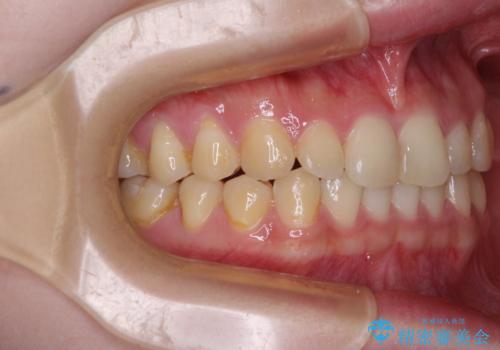

治療途中の奥歯と矯正治療の後戻り インビザライン・ライトによる矯正治療

- 根管治療を行ったままの奥歯と、矯正治療の後戻りを気にして来院された患者様です。

根管治療された歯に症状はなく、オールセラミッククラウンにて補綴治療を行うこととしました。

矯正治療の後戻りは軽微であったため、インビザラインの簡易パッケージであるインビザライン・ライトを用いて歯列を整えることとしました。

クラウンはよりよい咬み合わせで装着したいため、インビザラインを1セット使用して概ね歯列を整えた時点で補綴治療を行い、その後仕上げの矯正治療を行いました。